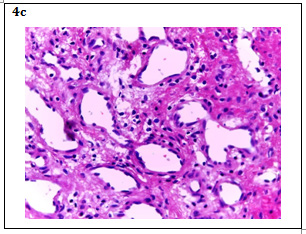

It is evident that they are benign mesenchymal tumors irrigated by the hepatic artery; they can be cavernous hemangiomas, when formed by large dilated vascular ducts with abundant stroma associated in turn to intravascular thrombosis and calcification that represent 80% of the cases. More rarely can be capillary hemangiomas formed by capillaries of thin wall with little stroma3 (Figure 4).

Figure 4 A: HE 4X Image: Empty spaces (channels) are observed and some with content, surrounded by scarce eosinophilic parenchyma.

B: HE 10X Image: It is observed that these channels are medium and large caliber blood vessels with endothelial lining of a single thin layer, in some of them are hematic content; The eosinophilic parenchyma corresponds to the hepatocytes that are being marginalized by vascular proliferation. Chronic inflammatory lymphocytic infiltrate is also observed around the blood vessels in response to the process of inflammation.

C: HE 40X Image: The endothelial cells that cover normal and dilated blood vessels, as well as the scarce parenchyma with some hepatocytes in degeneration and lymphocytic infiltrate, are more precisely observed.

Images from the department of Pathologic Anatomy, “Hospital Nacional Daniel Alcides Carrión”